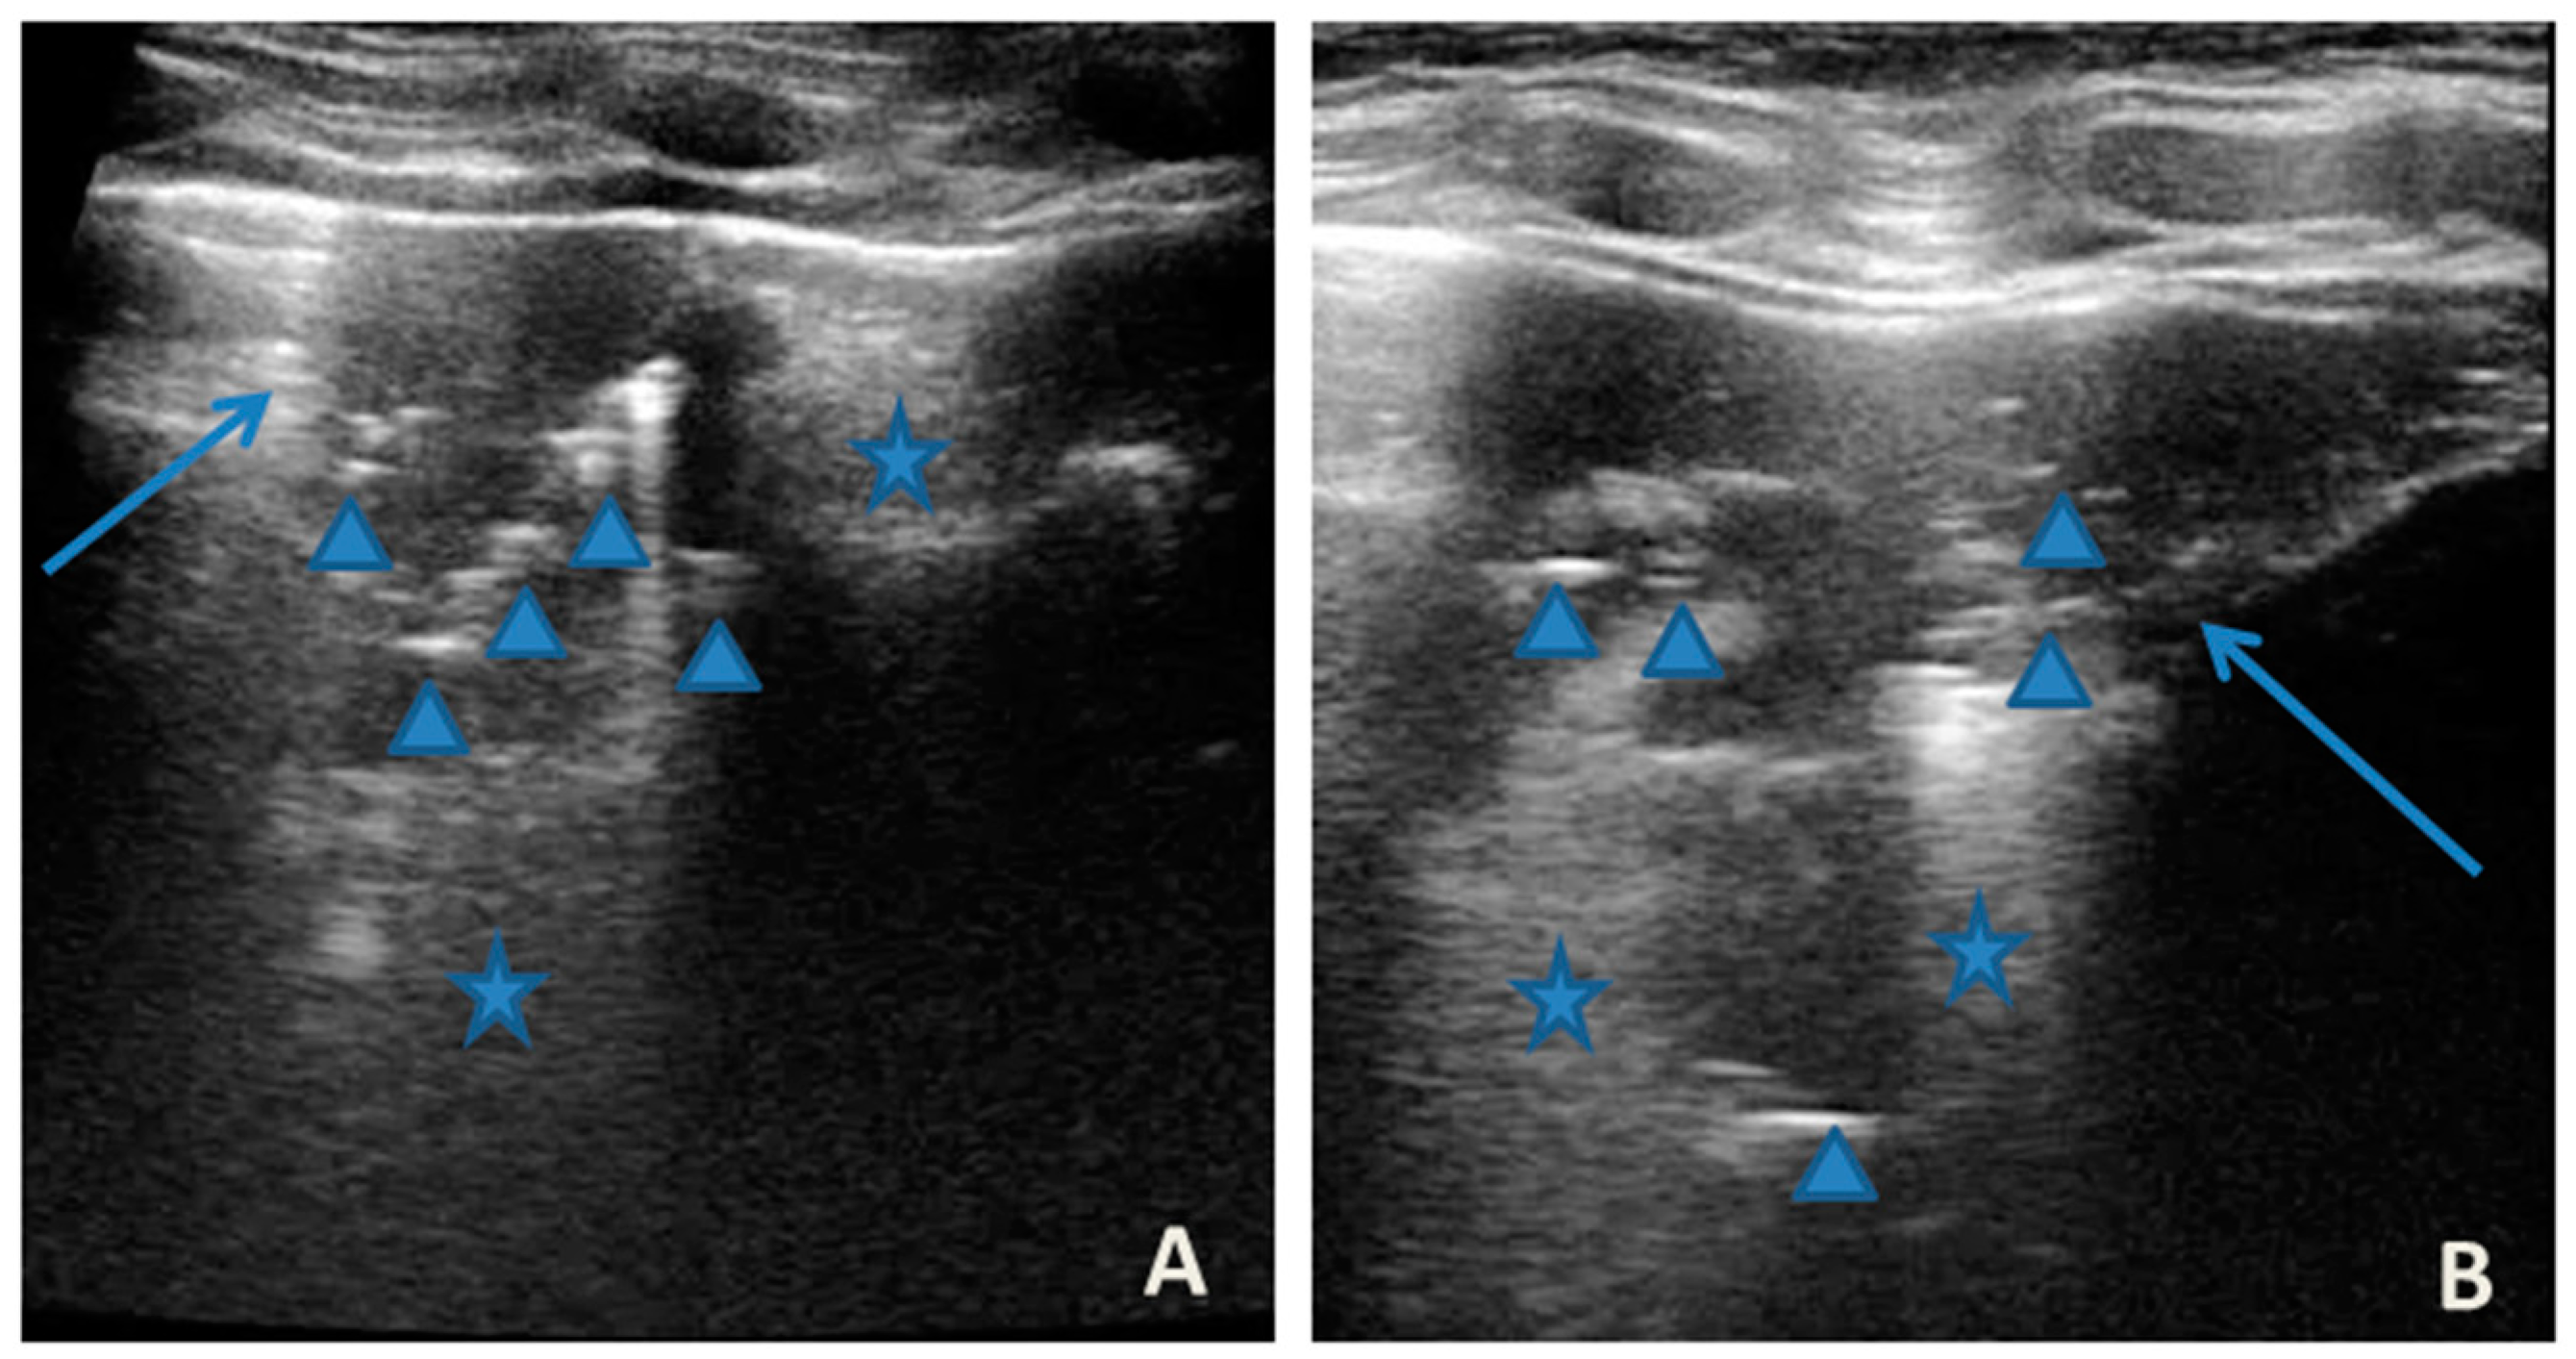

At our hospital, together with the clinical evaluation, we performed a lung ultrasound, which showed the presence of two areas of moderate lung atelectasis, in the right anterior mid-apical and in the left anterior paracardiac site, respectively, associated with sonographic interstitial syndrome (SIS) (Figure 1). LUS excluded the presence of inflammatory/infectious consolidations.

Figure 1.

Grayscale lung ultrasound examination shows: (A): on the right anterior field, mainly in the mid-apical area, consolidation of atelectasis origin (arrow) with static air bronchograms (punctate), and parallel to each other (arrowheads), associated with sonographic interstitial syndrome (SIS), represented by coalescent vertical artefacts or B-lines (asterisks); (B): on the left paracardiac site, consolidation of about 2.5–3 cm of atelectasis nature (arrow) with static air bronchograms (punctate) (arrowheads), associated with sonographic interstitial syndrome (SIS), represented by coalescent vertical artefacts or B-lines (asterisks).

The lung ultrasound follow-up showed complete resolution of the areas of atelectasis after 4 weeks from the start of background therapy, whereas the long vertical artifacts and irregularities of the pleural line persisted.

In our cases (Table 1), particularly in the first three cases—children with asthma not controlled due to an inadequate preventive therapy for age, phenotype, and severity of the clinical picture [1,2]—LUS was highly positive (Figure 1, Figure 3 and Figure 5). It showed the presence of lung atelectasis, which resolved slowly after weeks of therapy of the acute attack and the beginning of adequate preventive therapy. On the contrary, in case 4 and 5—children with asthma well controlled by adequate preventive therapy—LUS was not highly positive (Figure 6 and Figure 7). In fact, it did not show large atelectasis, but a slight SIS in case 4, and a SIS suggestive of viral infection of the small airways in case 5 [14,15].